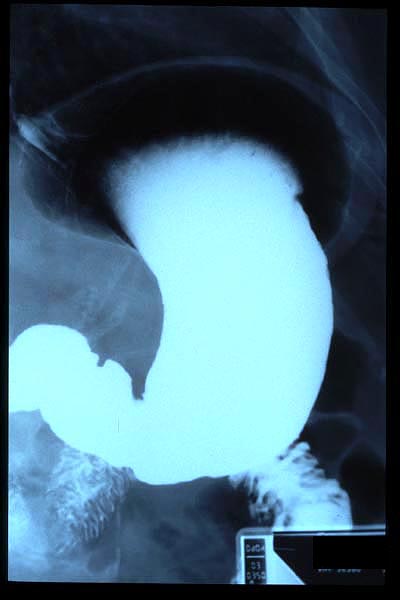

Hernia de hiato gigante.

Hernia de hiato por deslizamiento al TGED.

Hernia de hiato por deslizamiento al TEGD.